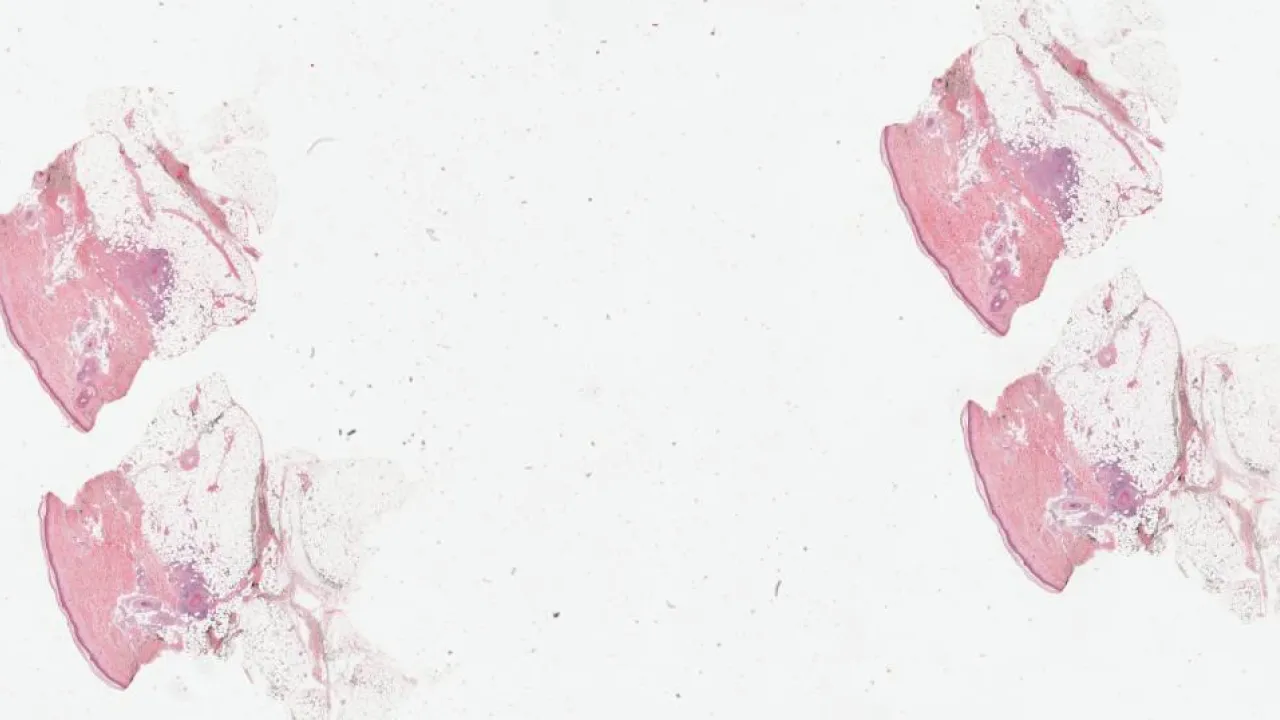

Skin, Diffuse large B-cell lymphoma, leg type

Skin, Follicular Lymphoma

Lymph Nodes, Castleman’s disease

Lymph Node, Hodgkin lymphoma, nodular sclerosis type

Thyroid, Medullary carcinoma

Pancreas, Solid pseudopapillary tumor

Lung, Small cell carcinoma

Pleura, Malignant mesothelioma, biphasic type

Bone, Chordoma

Ovary, Adult type granulosa cell tumor

Placenta, Complete hydatidiform mole

Esophagus, Granular cell tumour

Duodenum, Gastrointestinal stromal tumour

Stomach, Inflammatory fibroid polyp

Ovary, Low-grade serous carcinoma

Soft Tissue, Adenomatoid tumour

Breast, Invasive lobular carcinoma

Appendix, Sessile serrated adenoma

Uterus, Adenosarcoma

Endometrium, Placental site nodule

Skin, Polyarteritis nodosa

Ovary, Immature teratoma